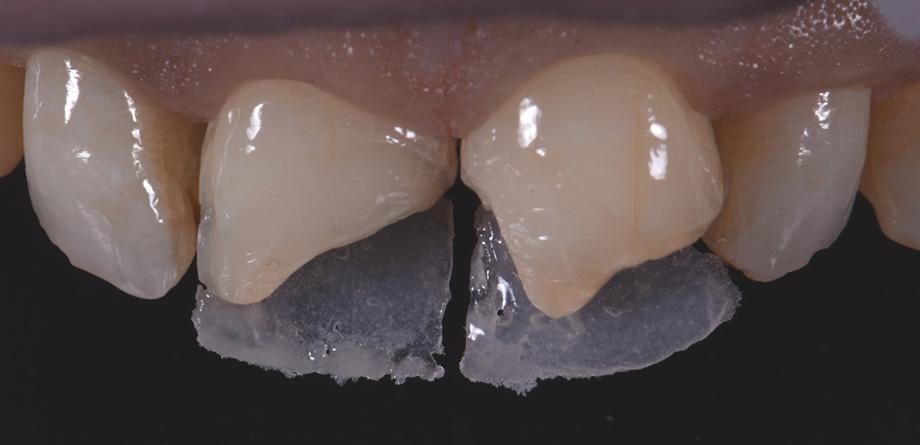

3 - Completion of the Palatal Shelf and interproximal wall with the application of G-ænial™ A’CHORD composite, shade JE. The Interproximal wall was formed with the use of a plastic mylar strip and pull through technique to help develop an anatomical contour.

4 - The dentine layer was then completed by the application of an opaque shade of G-ænial™ A’CHORD Shade AO2. This is to provide the correct opacity and “block out” effect of the final restoration.

5 - A chromatic body shade, G-ænial™ A’CHORD shade A2 was then applied and extended beyond the bevel to mask the transition line. Internal anatomy in the incisal third was also sculpted and formed in this increment of composite resin. White tints, Essentia White Modifier (WM) was then utilised to accentuate the mamelons and to replicate similar characteristics present in the adjacent right central incisor.